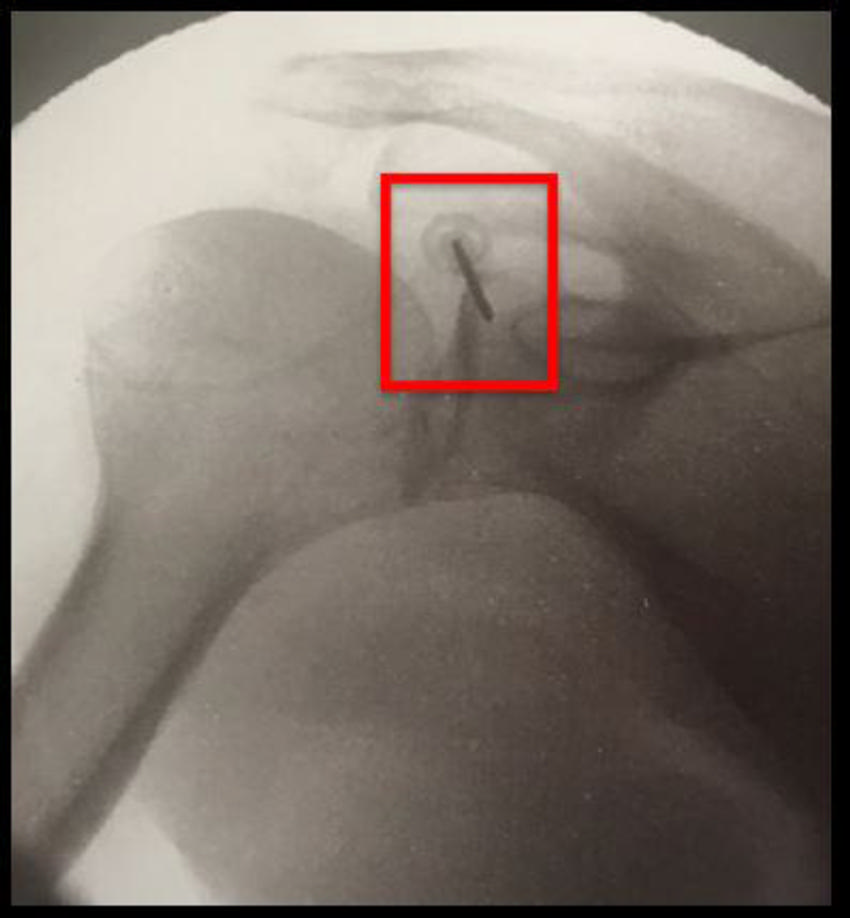

Figure 3. Shoulder-specific technique: there are five ablation targets

High-res (TIF) version

Figure 4. Suprascapular nerve cooled radiofrequency ablation targets.

Figure 6. Suprascapular nerve cooled radiofrequency ablation: Target #2

Figure 7. Axillary nerve cooled radiofrequency ablation: ablation targets.